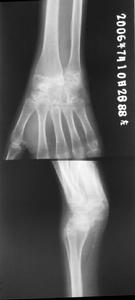

2.受累關節及胸部X線攝片、心電圖檢查。 必要時行超聲心動圖檢查。

①每日關節晨僵至少1h(≥6周);②3個或3個以上關節腫(≥6,周);③腕、掌指關節或近端指間關節腫(≥6周);④對稱性關節腫(≥6周);⑤皮下結節;⑥手X線片改變;⑦類風濕因子陽性(滴度>1∶32)。具備4條或4條以上標準,可確診。